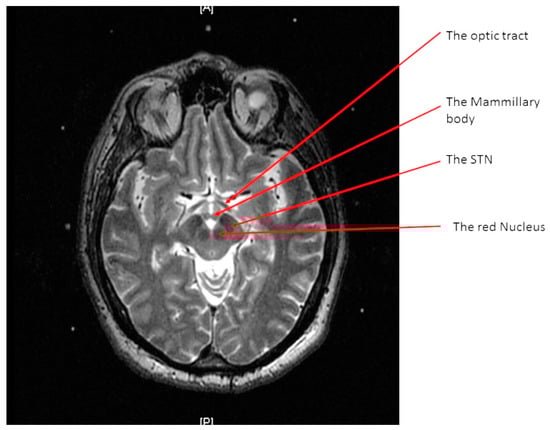

At the end of the scan, we chose an axial T2 image (or two adjacent images) in which both the AC and the PC are seen (Figure 3). With simple arithmetic equations based on the Leksell frame coordinates system, we were able to calculate the stereotactic coordinates of the mid-commissural point (MCP), and the STN directly from the MRI coordinates of the AC and the PC (Figure 4). Based on the known anatomical relationship of the STN to MCP from the previous anatomical studies and stereotactic atlases [36,47,48,49,50,51,52,53,54], we selected the STN target at 12 mm lateral, 3 mm posterior, and 6 mm inferior to the MCP.

Figure 3. An axial T2 weighted magnetic resonance imaging (MRI) image showing the anterior commissure and the posterior commissure.